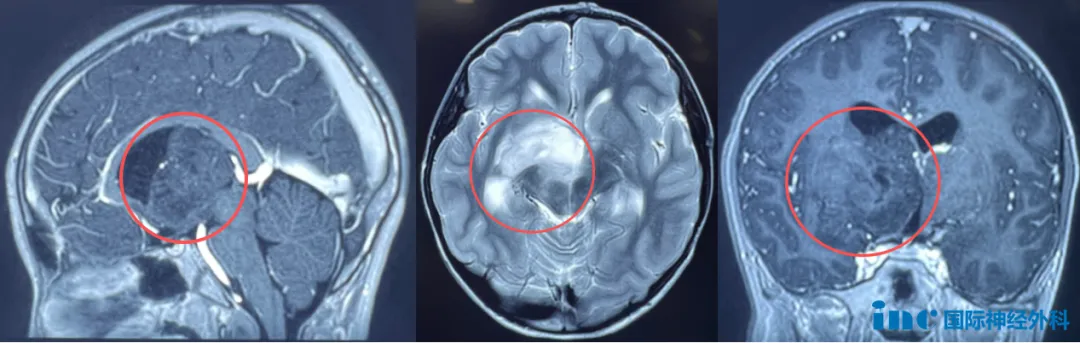

8岁男孩巨大丘脑-基底节占位

小航,右侧丘脑-基底节区出现占位性病变,肿瘤呈弥漫性生长趋势,脑室扩大,脑脊液循环已受影响。所幸,他目前尚未出现严重症状,仅偶有记忆力下降、注意力不集中和饮水呛咳。